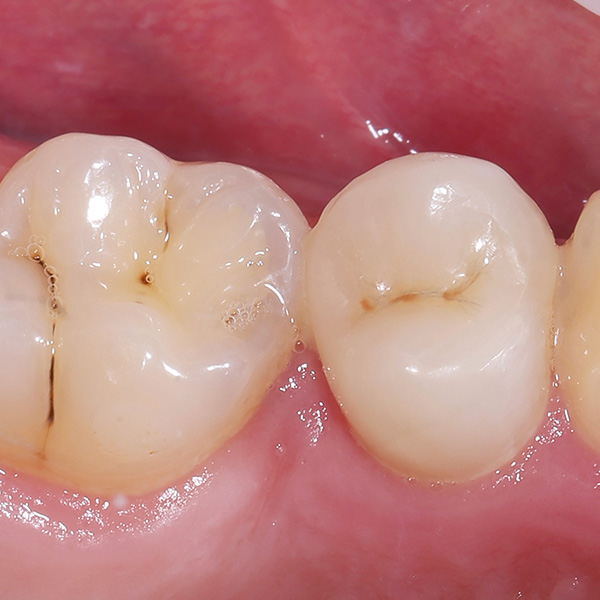

VITA ENAMIC multiColor Endokrone: Ausgangssituation vs. Finales Ergebnis

Ergebnis: VITA ENAMIC multiColor integrierte sich harmonisch in die natürliche Zahnsubstanz. Die insuffiziente Kompositfüllung an Zahn 14 (od) hatte zu Entzündungen im Zahnzwischenraum geführt.